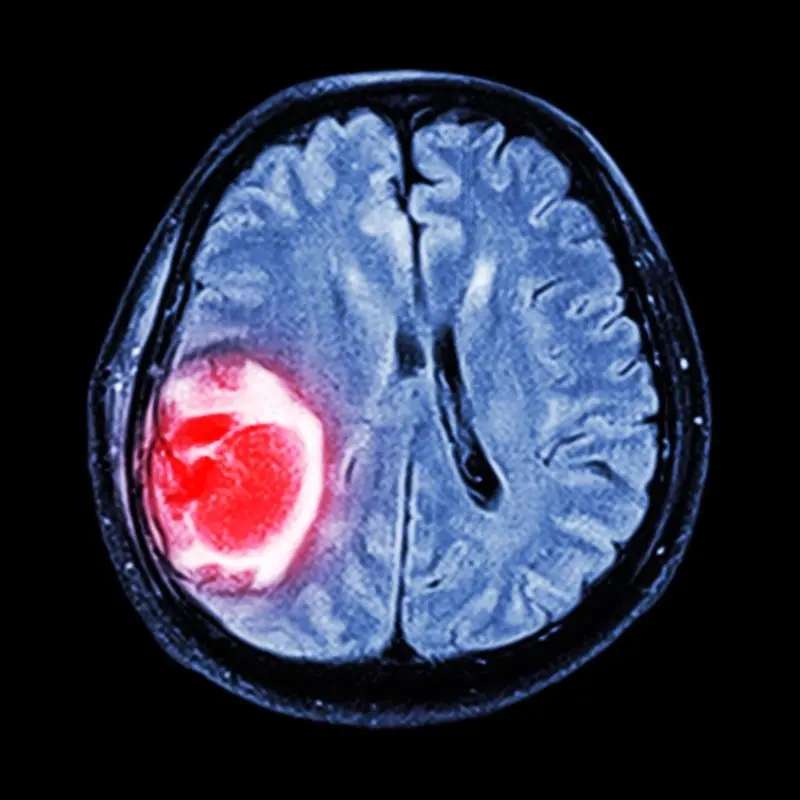

中枢神经系-统肿瘤:脑膜瘤、脑胶质瘤、垂体瘤、听神经瘤及星形细胞瘤等